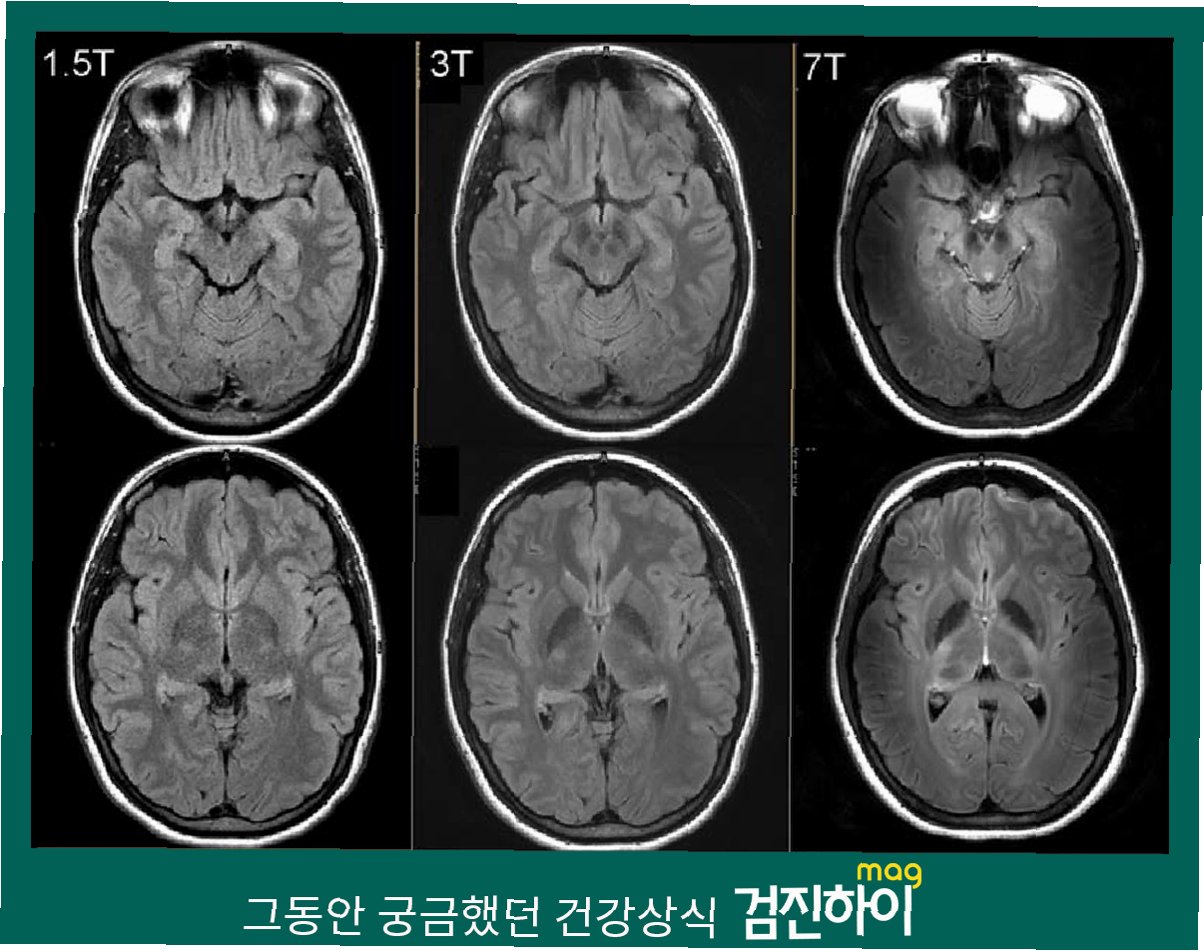

MRI 공포: 금속 목걸이, 죽음의 문턱으로… 당신의 안전을 위협하는 위험

MRI 검사, 당신의 안전을 위협하는 숨겨진 위험최근 미국에서 발생한 충격적인 사고는 우리에게 MRI 검사의 위험성을 다시 한번 상기시켜줍니다. 60대 남성이 금속 목걸이를 착용한 채 MRI 검사를 받다가 기기에 빨려 들어가 중태에 빠지는 사고가 발생한 것입니다. 이처럼 MRI 검사 시에는 작은 부주의가 생명을 위협하는 심각한 결과로 이어질 수 있습니다. 이번 사고는 MRI 검사의 안전 수칙 준수가 얼마나 중요한지를 강조하며, 우리 모두에게 경각심을 심어주고 있습니다. MRI 검사를 앞두고 있다면, 이 글을 통해 안전하게 검사를 받을 수 있도록 필요한 정보를 얻어가세요. 금속, MRI 검사에서 왜 치명적인 위험을 초래하는가?MRI(자기공명영상장치)는 강력한 자력을 이용하여 신체 내부를 촬영하는 의료..